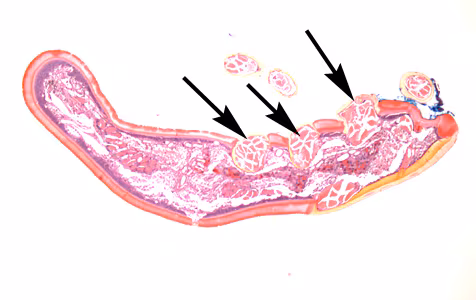

A skin biopsy specimen was collected from the clavicle region of a 45-year-old male who presented with what appeared to be a pigmented lesion. The patient resides in Kentucky and has no known international travel. The biopsy specimen was sent to Pathology for routine histologic work-up. Objects suggestive of an organism were examined on slides stained with hematoxylin-and-eosin (H&E). The attending pathologist captured images and sent them to CDC-DPDx for diagnostic assistance. Figures A–E represent five of the images received. What is your diagnosis? Based on what criteria?

Figure D